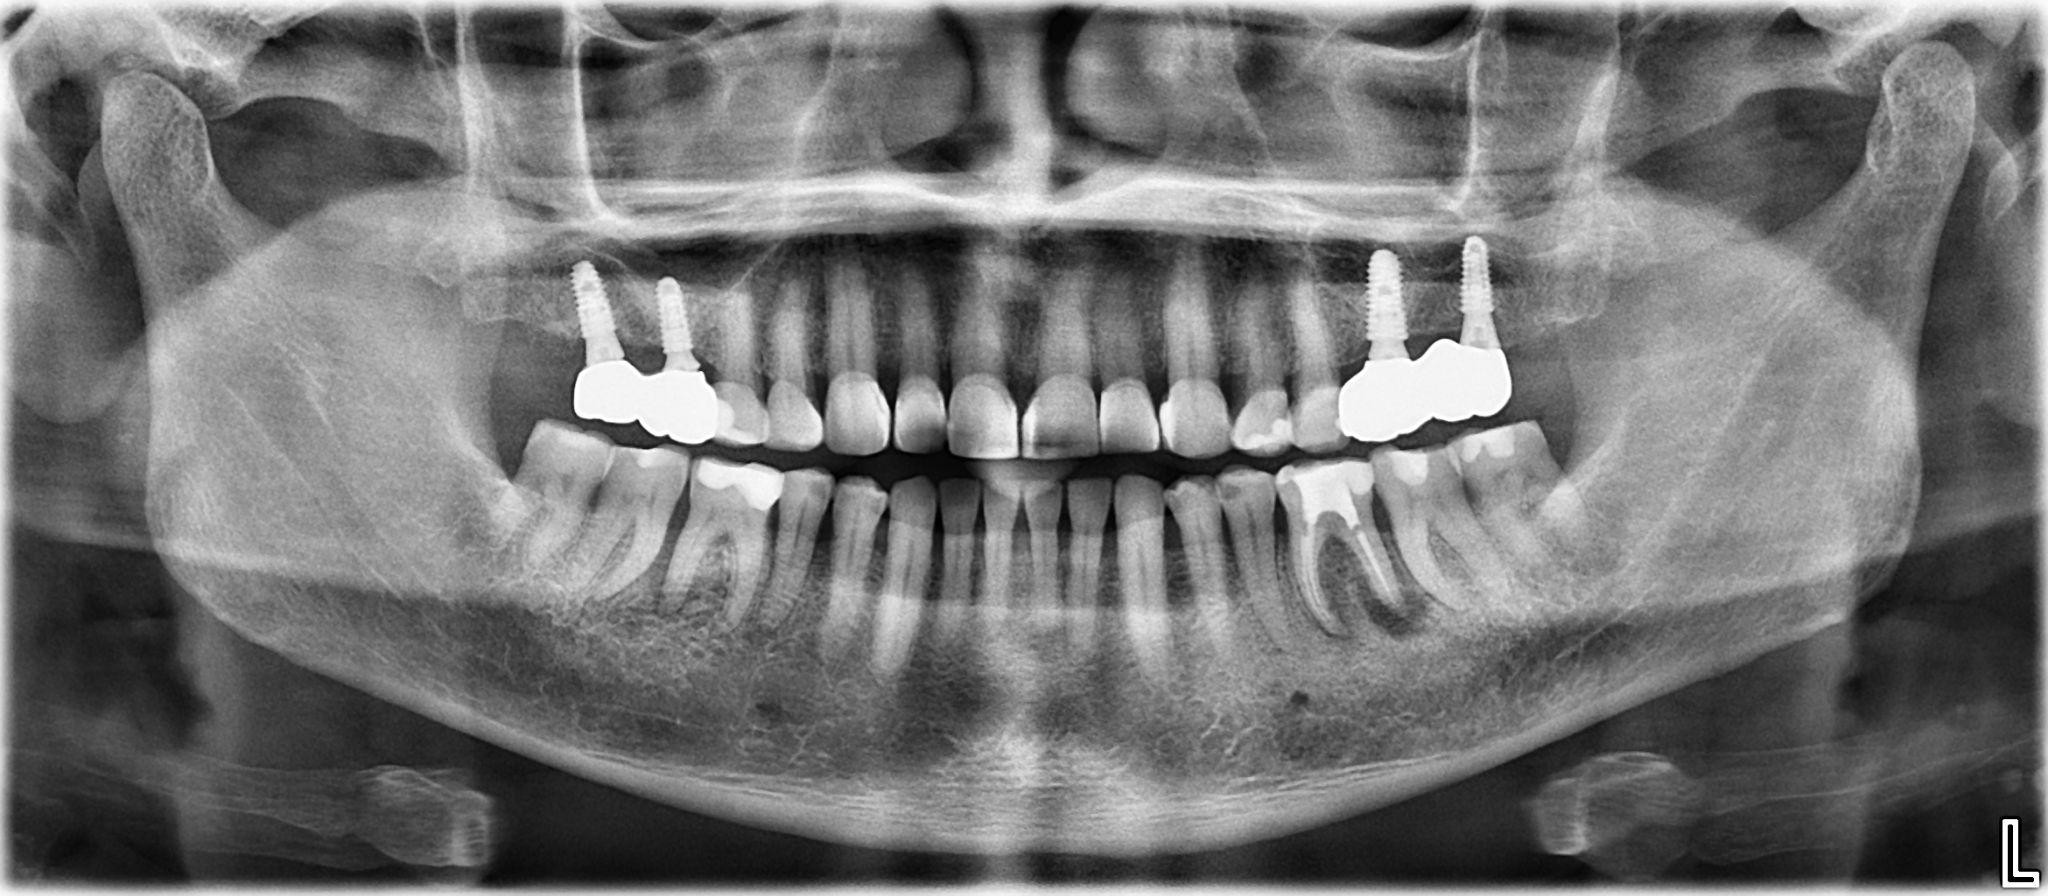

5. What option cannot be selected for the first quadrant of this panoramic X ray?

6 / 25

6. What option cannot be selected for the third quadrant of this panoramic X ray?

7 / 25

7. What option cannot be selected for the forth quadrant of this panoramic X ray?